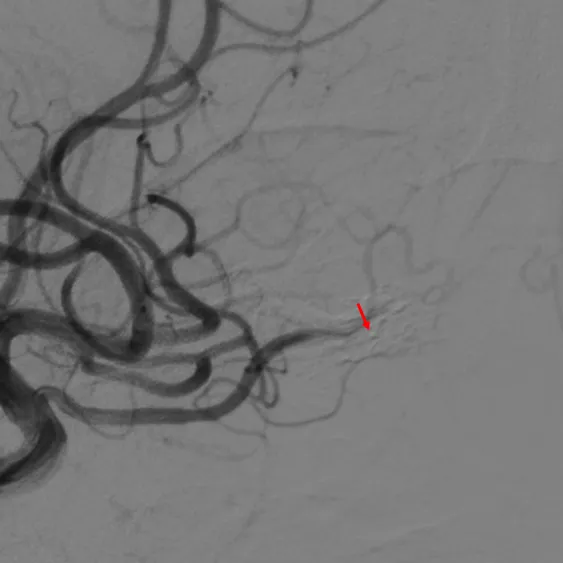

确认瘘口消失-右侧

确认瘘口消失-左侧

右颈总DSA确认瘘口消失、右视网膜染色正常。

左颈总DSA确认瘘口消失、左视网膜染色正常。